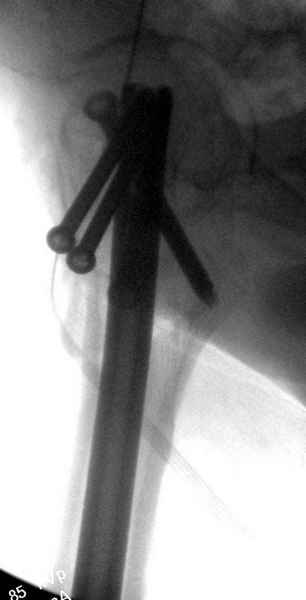

На второй день после выписки упал дома. Снимки приложены. Коллеги рекомендуют удаление шурупа и вытяжение. Что делать?

Привет из солнечного Будапешта с Eurotrauma-2008. Да, замечательный пример. Получается, профилактику расхождения отломков шейки надо было проводить каким-то реконструкционным или проксимальным гвоздем, причем сразу длинной версией. Сейчас, наверно, так и надо бы сделать.

Убрать винты, каким-то джойстиком в вертельной области сделать репозицию шейки, фиксировать ее спицами, а дальше вправлять и фиксировать как вертельный перелом.

Правильно, ситуация изменилась, как говорят у нас теперь "different animal", надо решать проблему подвертельного перелома. При наличии различных вариантов фиксаторов, включая Страйкер Гамма 3, мы выбрали DePuy Antegrade Trachanteric Nail из-за многовариантности проксимальной фиксации и двойного изгиба. Вводится через вертел под 8 градусным углом, и есть достаточный передний диафизарный изгиб, предупреждающий пенетрацию дистального переднего кортекса.

Но ведь и головка бедра сползла в варус - отчего ограничились только фиксацией подвертельного перелома, а не убрали винты и не сделали репозицию шейки?